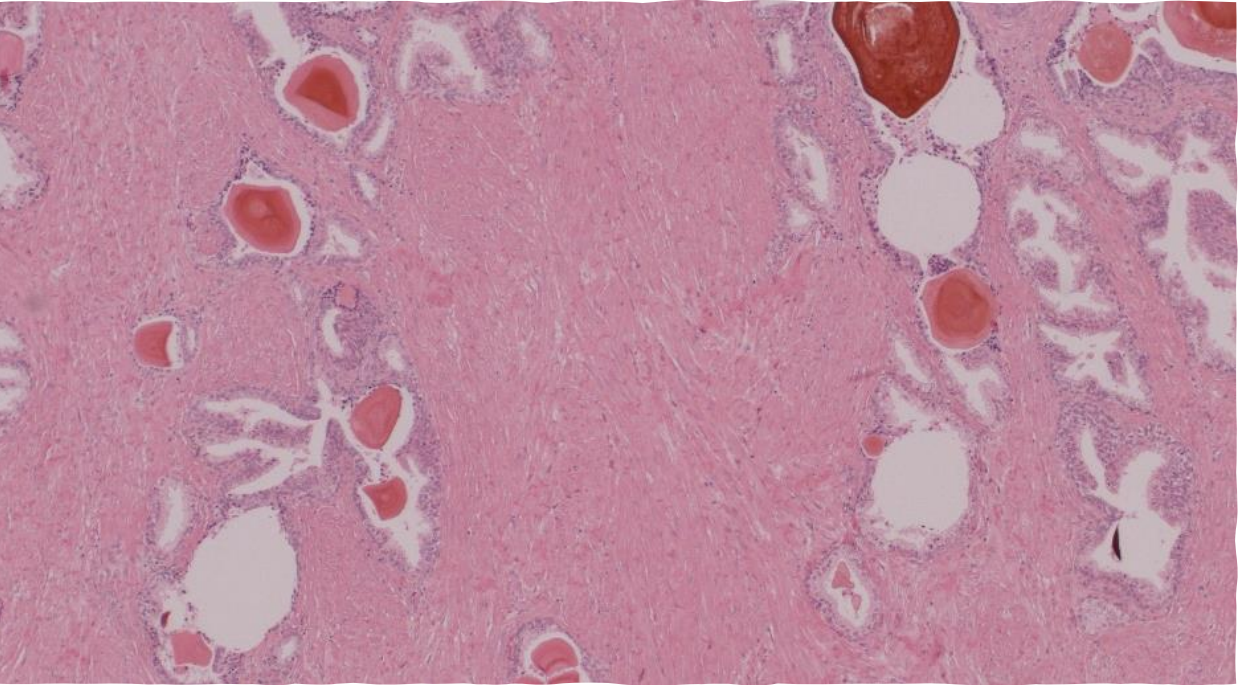

Spongy bone